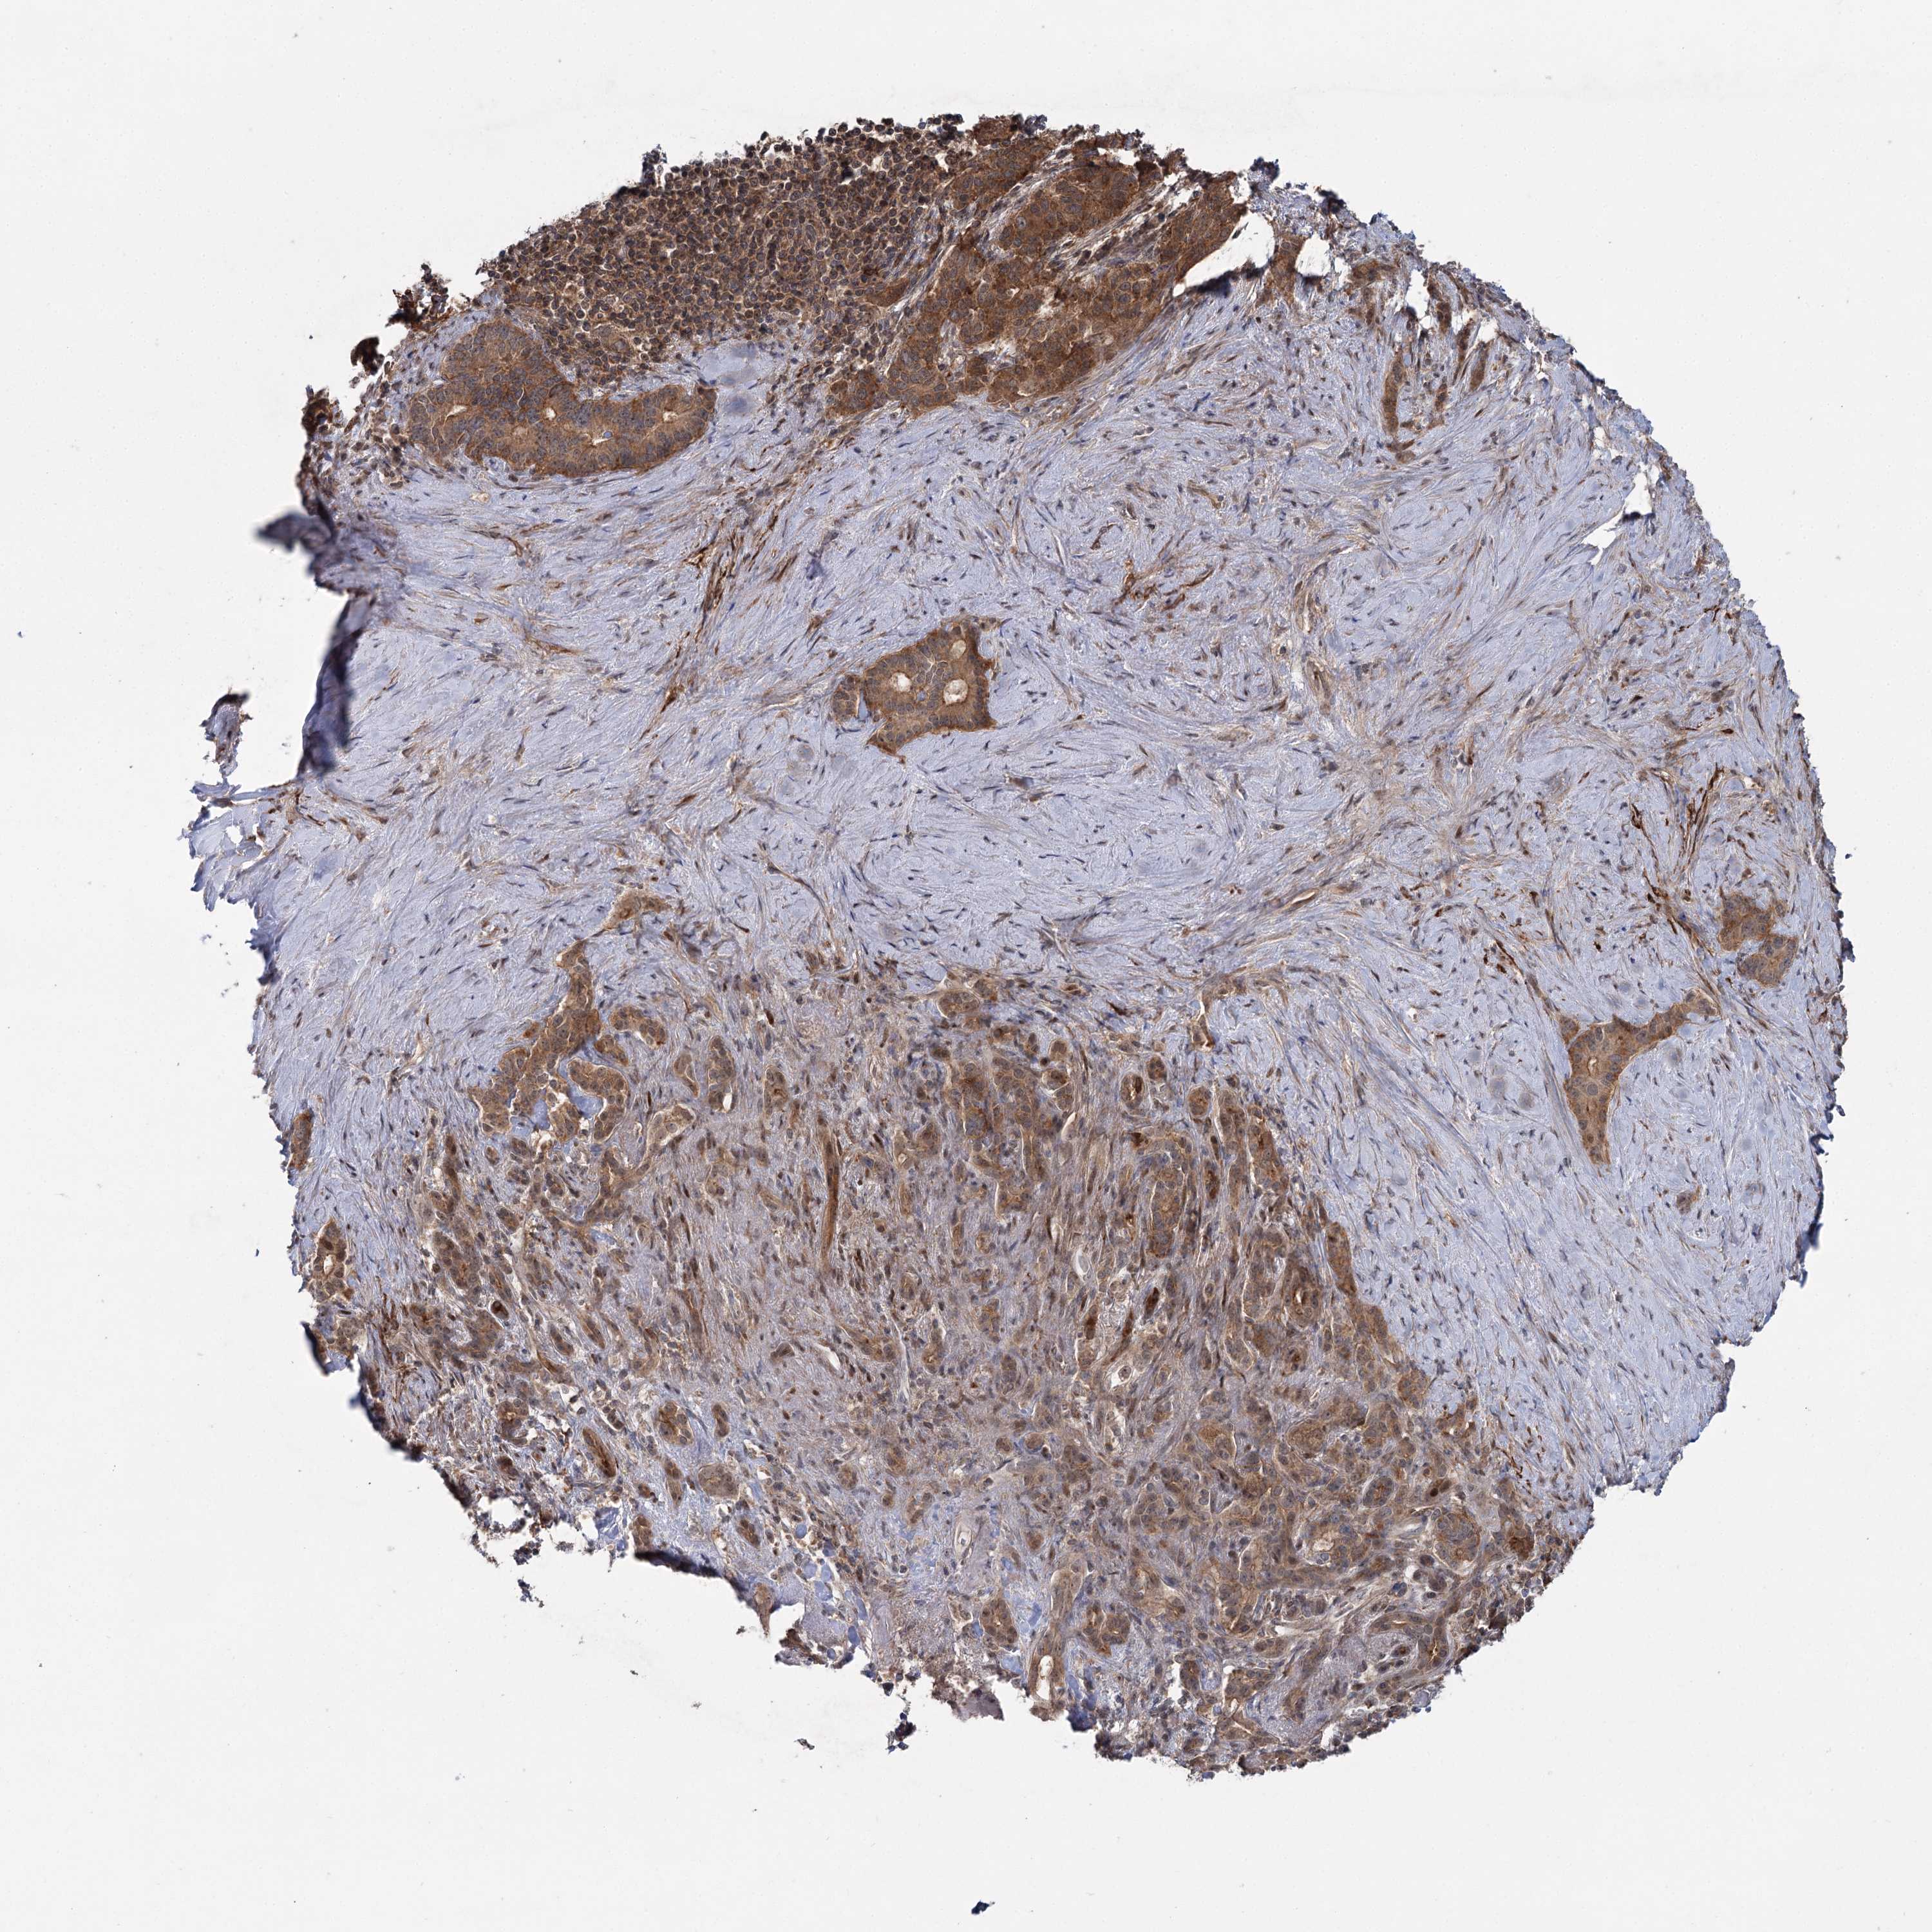

PANCREATIC CANCER - Protein expressioni

A mouse-over function shows sample information and annotation data. Click on an image to view it in a full screen mode. Samples can be filtered based on level of antibody staining by selecting one or several of the following categories: high, medium, low and not detected. The assay and annotation is described here.

Note that samples used for immunohistochemistry by the Human Protein Atlas do not correspond to samples in the TCGA dataset.

Antibody stainingi

Antibody staining in the annotated cell types in the current human tissue is reported as not detected, low, medium, or high, based on conventional immunohistochemistry profiling in selected tissues. This score is based on the combination of the staining intensity and fraction of stained cells.

Each image is clickable and will lead to virtual microscopy that enables deeper exploration of all samples and also displays staining intensity scores, fraction scores and subcellular localization as well as patient and tissue information for each sample.

Antibody HPA038084

Staining

High

Medium

Low

Not detected

Intensity

Strong

Moderate

Weak

Negative

Quantity

>75%

75%-25%

<25%

None

Location

Nuclear

Cytoplasmic/membranous

Cytoplasmic/membranous,nuclear

Adenocarcinoma, NOS